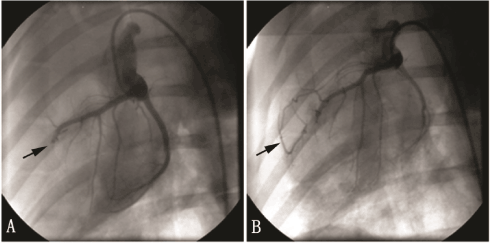

ECG showed that the ST segment of the chest leads elevated in all pigs after the LAD ligation. CAG proved that LAD ligation was successfully performed with total occlusion in every established AMI model (Figure 1). The cTnI levels of all animals were > 0.1ng/ml except 1 in positive control group and 1 in high-dose Tongxinluo group. One pig in the high-dose group died 25 days after the LAD ligation.

Figure 1. Coronary angiogram of the pig AMI model. A: arrow indicates proximal LAD totally occluded after LAD ligation. B: arrow indicates the collateral vessels formed and the distal LAD showed up although the proximal LAD still occluded 1 month after the establishment of the AMI model.